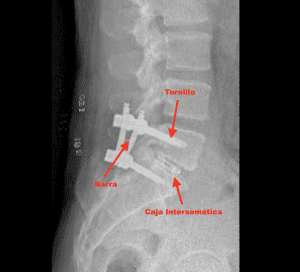

Colocación del dispositivo intersomático, tornillos transpediculares y barra

Una vez colocado el injerto óseo, se inserta un dispositivo intersomático entre las vértebras afectadas. Esto ayuda a mantener el espacio adecuado y proporciona soporte adicional a la estructura vertebral.

Colocación tornillos, barras y tuercas

Finalmente a través de otras pequeñas incisiones de aproximadamente 1 cm, se colocan tornillos transpediculares y sobre los tornillos se introduce una barra para estabilizar la columna y asegurar la correcta fusión de las vértebras. Este hardware proporciona una fijación firme, permitiendo una mejor recuperación postoperatoria y facilitando el proceso de fusión ósea.

Radiografía lateral de una artrodesis L5-S1 por endoscopia